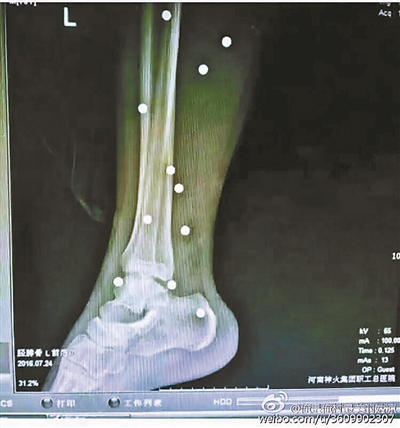

傷者體內(nèi)取出的鋼珠

爆炸導(dǎo)致鋼珠遍布傷者身體各處

黃明的伯伯對(duì)北青報(bào)記者表示,由于黃明直接踩到了爆炸物,所以傷情最為嚴(yán)重,“他的腿被炸斷,身體內(nèi)被炸進(jìn)了40多顆鋼珠。手術(shù)后已經(jīng)從體內(nèi)取出29顆鋼珠,還有十多顆鋼珠沒有取出來。”根據(jù)黃明的入院記錄,他全身有多處爆炸傷,且全身多處異物存留。

爆炸發(fā)生時(shí),陳浩的位置與黃明靠得很近,因此也受傷較重。他告訴北青報(bào)記者,經(jīng)過10多個(gè)小時(shí)的手術(shù)后,醫(yī)生從他身體里取出了12顆鋼珠。目前,他和黃明兩人經(jīng)過手術(shù)后,已從重癥監(jiān)護(hù)室轉(zhuǎn)至普通病房。其余三人中,陳剛的臀部受傷,當(dāng)天晚上在醫(yī)院清理完傷口后便回了家,而同行的兩名女生身上有一些擦傷。